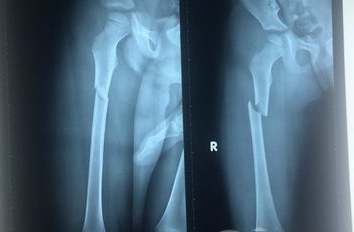

| Phim chụp chân phải của Thiện bị cha dượng và mẹ đánh gãy. Ảnh: Khánh Trung. |

Trước đó, vào sáng 10/8, Thiện được cha dượng Nguyễn Văn Ngờ Em (25 tuổi) và mẹ là Sơn Thị Sa Hương (24 tuổi) đưa đến Bệnh viện Chấn thương chỉnh hình TP HCM trong tình trạng bầm tím toàn thân. Kết quả chụp X-quang cho thấy, chân phải của bé gãy xương ở khớp háng.